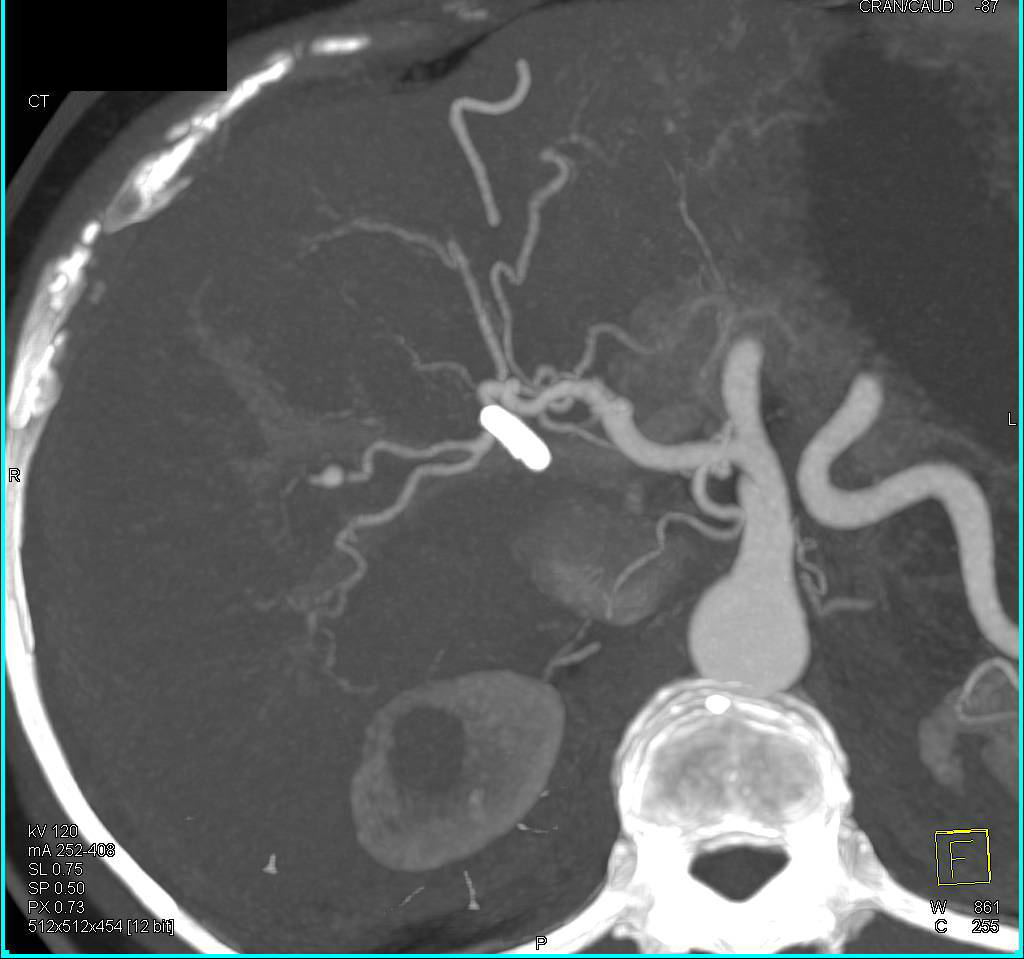

Recurrent Hepatocellular Carcinoma (Hepatoma) s/p Resection